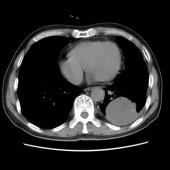

[影像描述]

左肺下叶可见高密度肿块影,边界清晰,边缘不规则,左肺下叶支气管局部截断,增强后病灶边缘轻度强化,中心未见明显强化;左侧胸腔内可见液性密度影;纵隔内未见明确肿大淋巴结影。